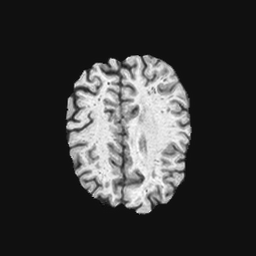

Exp. 1: Segmented adult brain data is used to evaluate our network’s regression performance with known ground truth Tisubscript𝑇𝑖T_{i}. 85 brains from the ADNI data set[1] were randomly selected; 70 brains for ΩtrainsubscriptΩ𝑡𝑟𝑎𝑖𝑛\Omega_{train} and 15 brains for ΩvalidationsubscriptΩ𝑣𝑎𝑙𝑖𝑑𝑎𝑡𝑖𝑜𝑛\Omega_{validation}. Fig. 2 shows an example slice of the ground truth and the reconstructed ΩΩ\Omega.

Refer to caption

(a)

(b)

(c)

(d)

Figure 2: Example slice from the segmented adult brain MRI data set (a); reconstruction from 300 ωisubscript𝜔𝑖\omega_{i} based on SVRNet regression without SVR (b); SVR initialised with SVRNet predictions after eight iterations of SVR (c). Note that SVRNet (b) predicts individual slice transformations only from image intensities without any initial world co-ordinates of the sampled slice. (d) shows the achieved PSNR in dB when comparing the volumes of (b) and (c) to (a).

Reconstructing from Ti^^subscript𝑇𝑖\hat{T_{i}} initialisation without SVR yields a PSNR of 23.7 ±plus-or-minus\pm 1.09; with subsequent SVR the PSNR increases to 29.5±plus-or-minus\pm2.43 when tested on 15 randomly selected test volumes after four iterations of SVR.